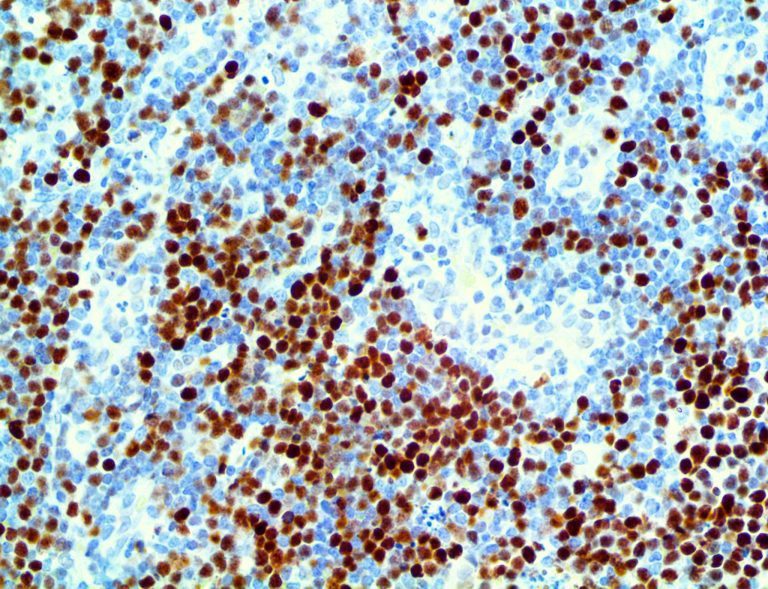

It is the ICU physician who is most likely to witness one of the deadliest manifestations of the abnormal immunological response, the cytokine storm syndrome (CSS). This response is also referred to by some as the cytokine release syndrome (CRS). CSS is characterized by continuous activation and expansion of macrophage and lymphocyte populations, which secrete large amounts of cytokines, causing the cytokine storm. This massive cytokine release is akin to hemophagocytic lymphohistiocytosis (HLH) disease, a syndrome characterized by initial unchecked and persistent activation of cytotoxic T lymphocytes and NK cells.

Clinical and laboratory manifestations of HLH include fever, enlarged liver and/or spleen, neurologic dysfunction, coagulopathy, liver dysfunction, cytopenias (i.e., low levels of erythrocytes, leukocytes, and/or platelets), hypertriglyceridemia, hyperferritinemia, hemophagocytosis, and eventually diminished NK cell activity as the immune system becomes progressively paralyzed. HLH can be familial (primary HLH) or secondary to another disease process (sHLH), such as rheumatic disease, in which it is referred to as macrophage activation syndrome (MAS, characterized by elevated ferritin).